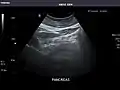

Left kidney

Kidneys: Right and left kidneys measure 11.5 cm and 12 cm in length respectively. No hydronephrosis. Small left lower pole kidney cyst.